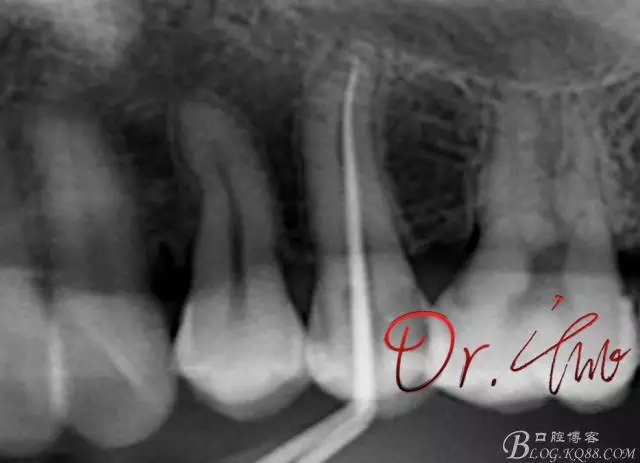

重點第二例病例,初診

拍片確定長度

試主尖,近中頰側(cè)形成臺階

試主尖,近中頰側(cè)再次拍片查看臺階位置及確定長度